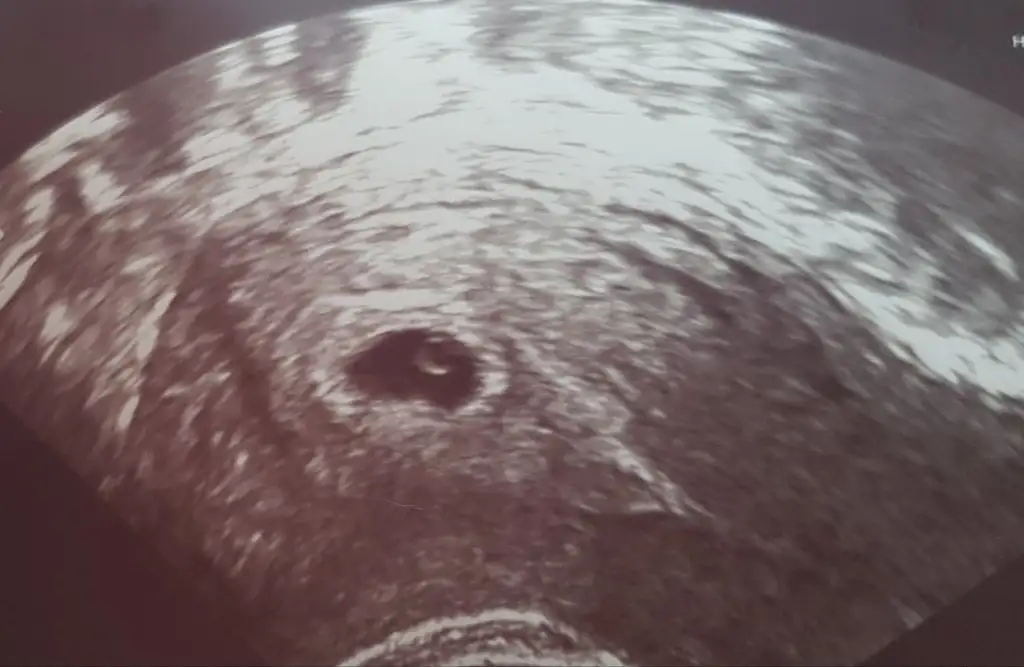

Maşallah darısı bizeBu da dünden ilk fotoğrafımıııız![]()

Kızlar çok şükür keseyi gördük ve yolk u. Sırada kalp atışı var. Rabbim hepimize nasip etsin![]()